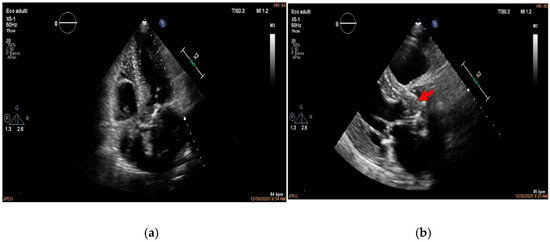

Multimodality Imaging in Infective Endocarditis: A Clinical Approach to Diagnosis

by Leonardo Brugiatelli, Francesca Patani, Carla Lofiego, Martina Benedetti, Irene Capodaglio, Pongetti Giulia, Francioni Matteo, Paolini Enrico, Nazziconi Marco, Kevin Maurizi, Furlani Giulia, Massari Arianna, Luciani Simone, Anselmi Benedetta, Gatti Chiara, Schicchi Nicolò, Fogante Marco, Tarsi Giovanni, Dello Russo Antonio, Di Eusanio Marco, Marini Marco and Fabio Vagnarelliadd Show full author list remove Hide full author list

Medicina 2025, 61(12), 2241; https://doi.org/10.3390/medicina61122241 - 18 Dec 2025

Infective endocarditis (IE) is a life-threatening condition with a rising incidence, demanding rapid and precise diagnosis. While echocardiography remains the cornerstone of initial evaluation, its limitations in complex cases—such as those involving prosthetic valves or cardiac devices—are well-known. This review synthesizes current evidence [...] Read more.

Infective endocarditis (IE) is a life-threatening condition with a rising incidence, demanding rapid and precise diagnosis. While echocardiography remains the cornerstone of initial evaluation, its limitations in complex cases—such as those involving prosthetic valves or cardiac devices—are well-known. This review synthesizes current evidence and guidelines to outline a practical, multimodality imaging approach for IE. We emphasize that integrating advanced techniques like cardiac computed tomography (CT) and [18F]-fluorodeoxyglucose positron emission tomography/computed tomography (FDG PET/CT) early in the diagnostic pathway, particularly in high-risk scenarios, significantly enhances diagnostic certainty, guides therapeutic decisions, and improves patient outcomes. A tailored imaging strategy, driven by clinical presentation and integrated within a multidisciplinary endocarditis team, is paramount for modern IE management. Full article

(This article belongs to the Special Issue Diagnosis and Treatment of Valvular Heart Diseases)

Show Figures

Figure 1